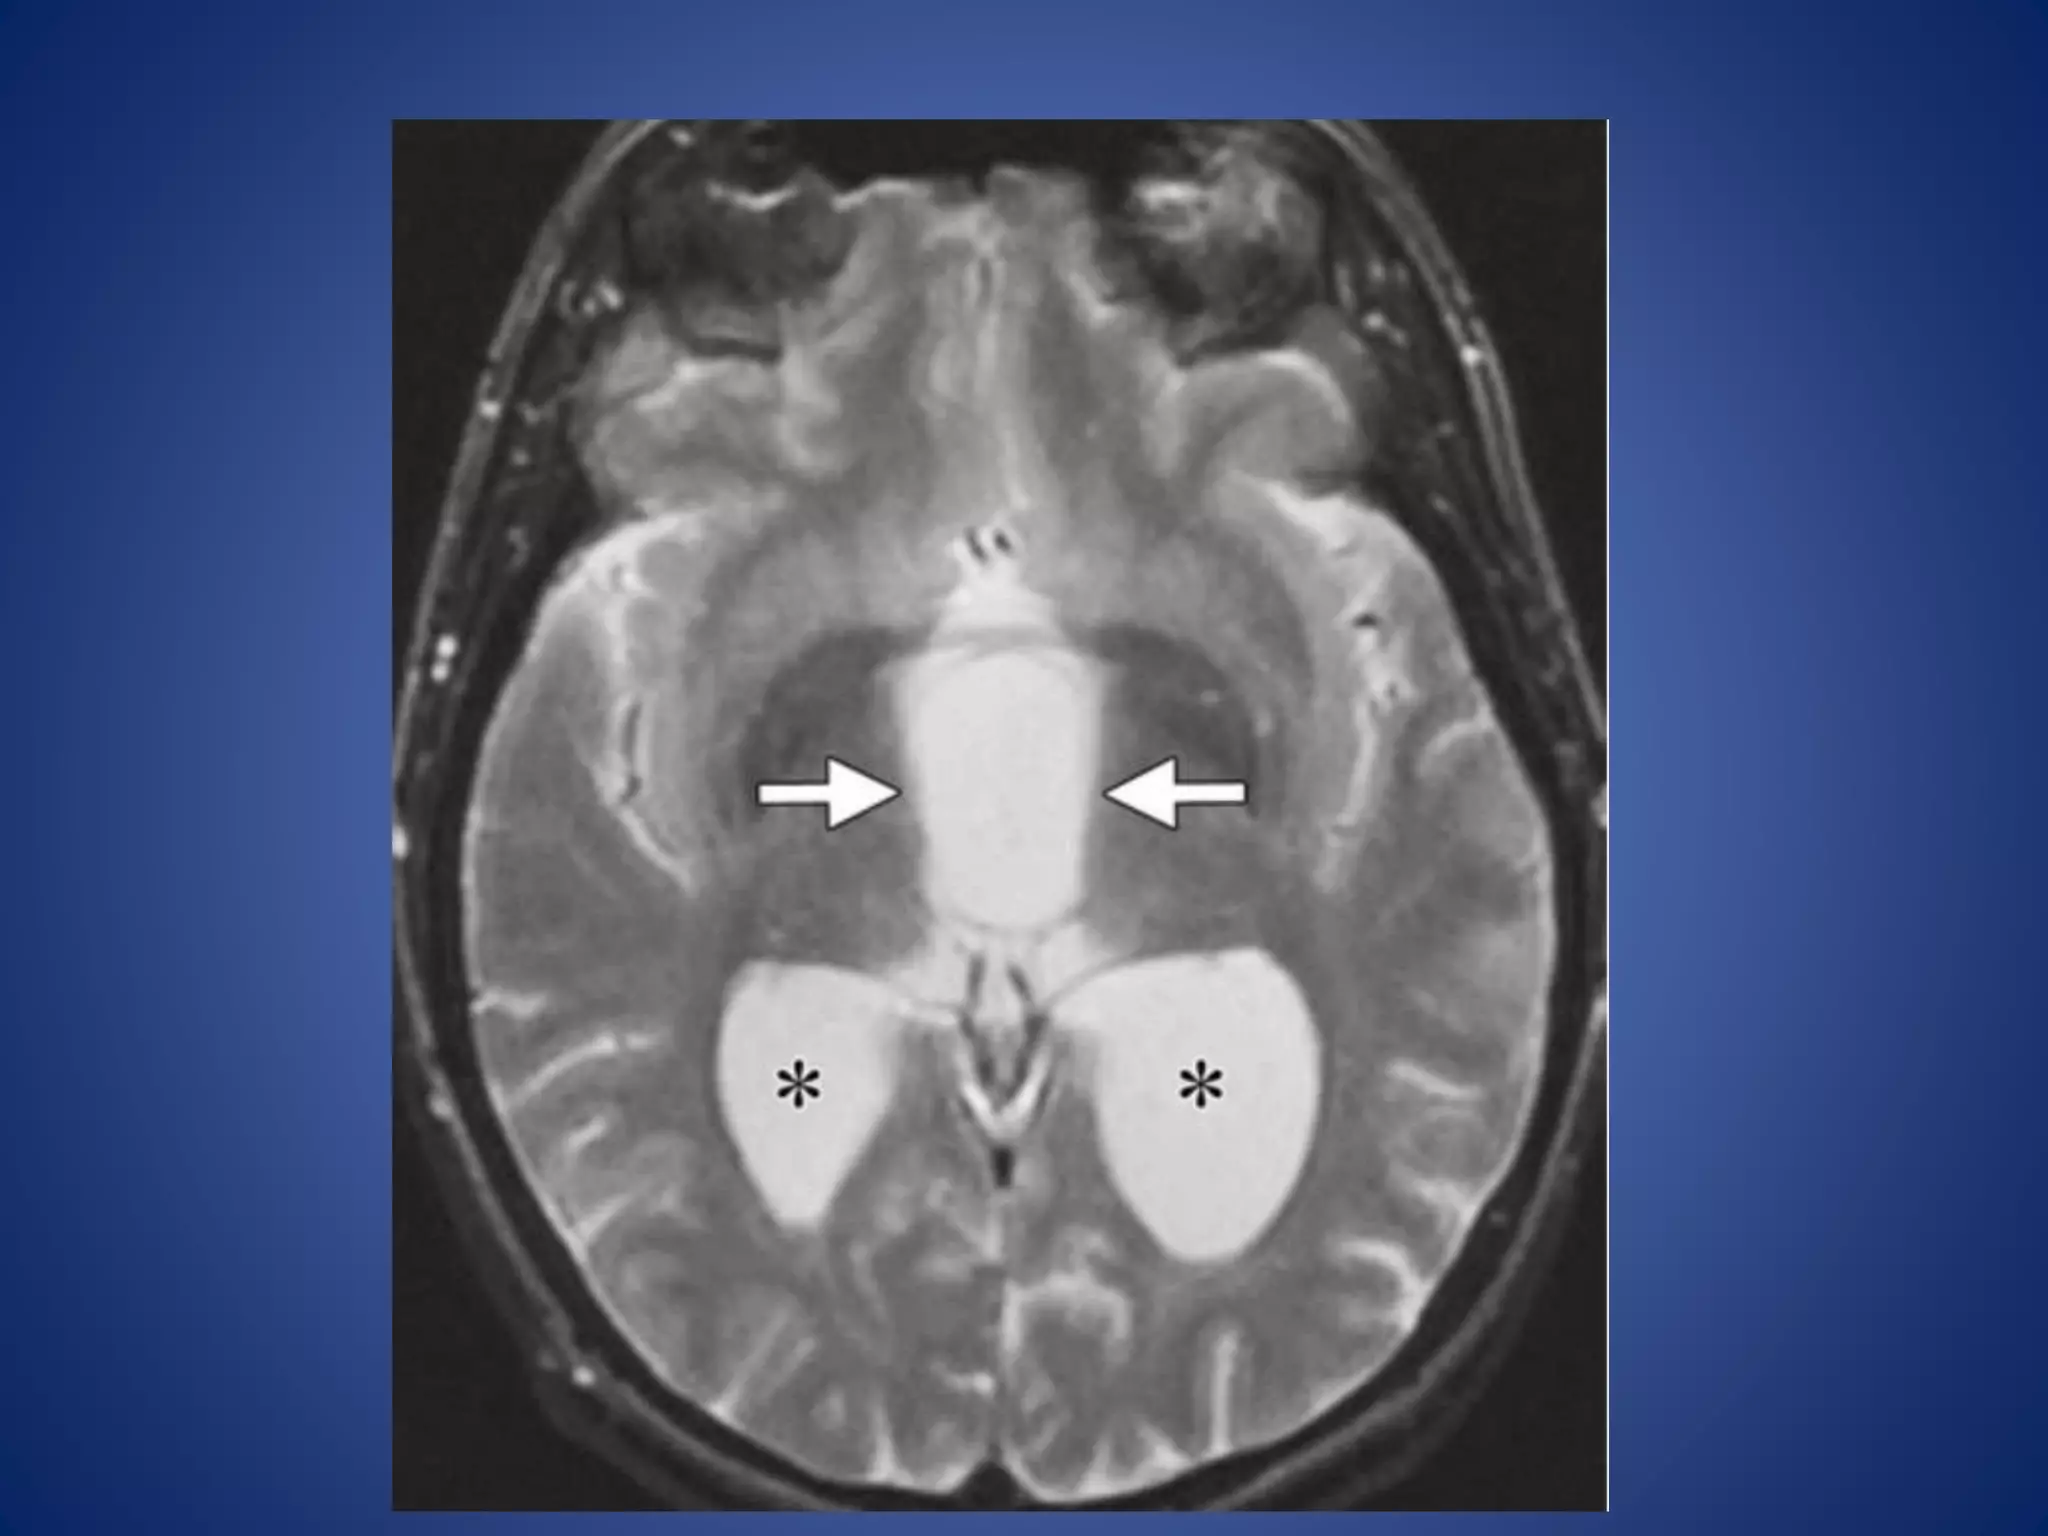

• #25 (b) Axial T2WI, the cyst (arrows) is homogeneous and isointense relative to cerebrospinal fluid. The lateral ventricles (*) are dilated due to obstruction by the cyst.

• #26 the cyst (arrows) demonstrates no enhancement